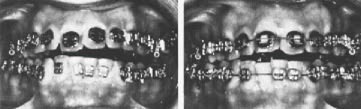

Fig. 9 Case 1. Before mandibular advancement and two weeks after release of intermaxillary fixation.

Fig. 13 Case 2. Occlusion six months after surgery.